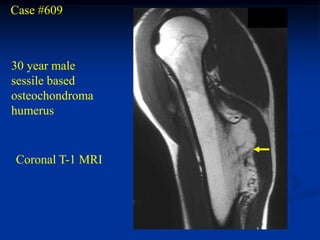

Case #609

30 year male

sessile based

osteochondroma

humerus

Coronal T-1 MRI